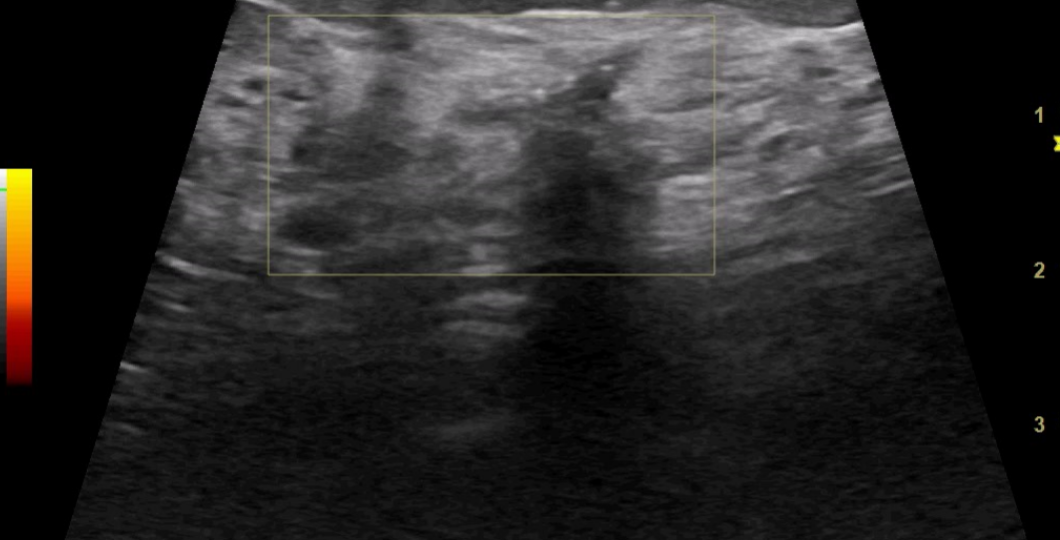

УЗИ на приеме от 20.08.24г:

На 3 ч на расстоянии 4 см от соска определяется гипоэхогенная зона с нечеткими неровными контурами размером 20х13 мм, с гиперэхогенными включениями, и цветовыми сигналами BI-RADS 4b. Был запрошен CD диск с маммограммами для второго мнения. Второе прочтение, заключение: в верхне-наружном квадранте левой молочной железы на границе с ретромаммарной зоной на расстоянии 6 см от соска, определяется зона нарушения архитектоники на участке 35х40 мм